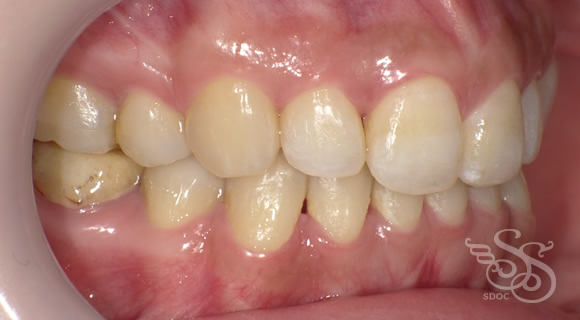

左側:術前

左側:術後